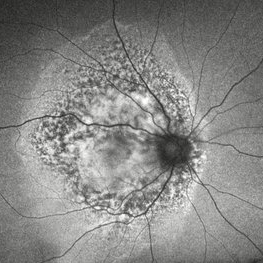

Idiopathic Uveal Effusion Syndrome

Idiopathic Uveal Effusion Syndrome

Aug 22 2024 by Jordyn Beckman

61 year old male with Idiopathic Uveal Effusion Syndrome with starry night appearance on fluorescein. 3 weeks s/p single external drainage retinotomy and 9 weeks of oral pred with recurrent choroidal effusions. Has since returned to surgery for secondary drainage retinotomy; subretinal fluid remain persistent.

Photographer: Jordyn Beckman

Imaging device: Optos California

Condition/keywords: chorioretinitis, Choroidal, exudative detachment, window defect